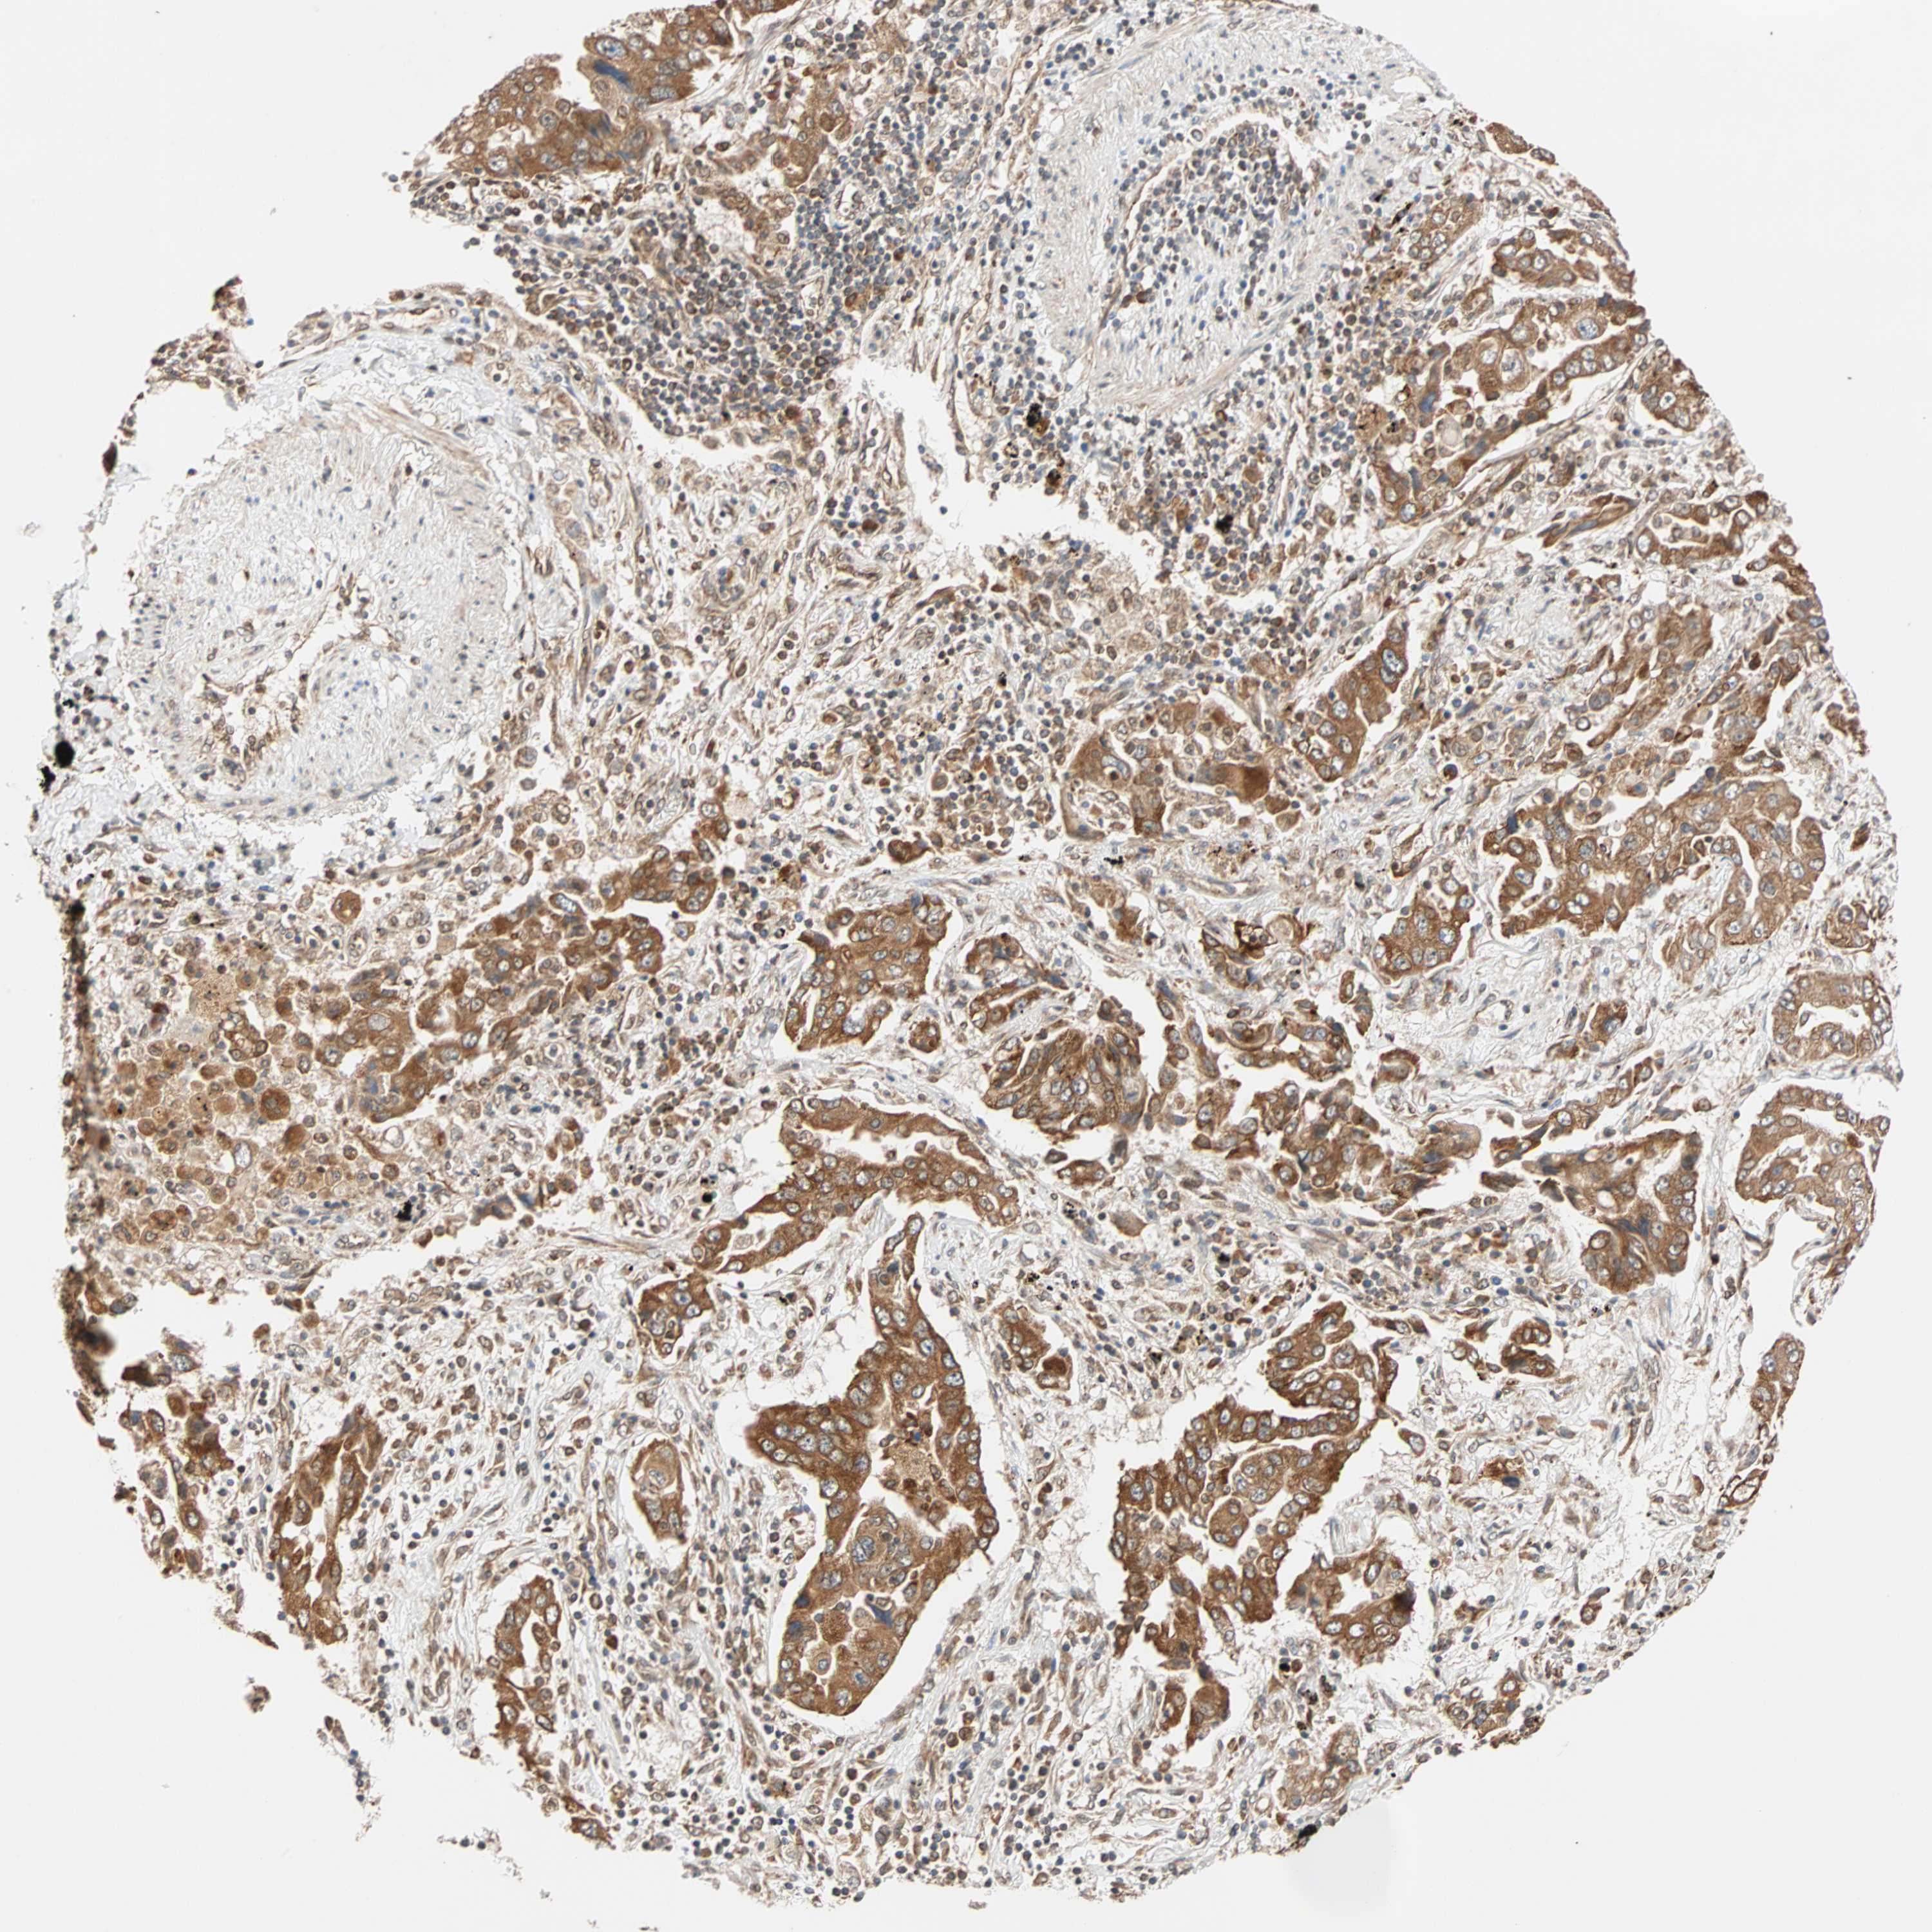

CANCER LUNG CANCER Show tissue menu

LUAD TCGA LUAD VALIDATION LUSC TCGA LUSC VALIDATION PROTEIN LUAD CPTAC PROTEIN LUSC CPTAC PROTEIN EXPRESSION